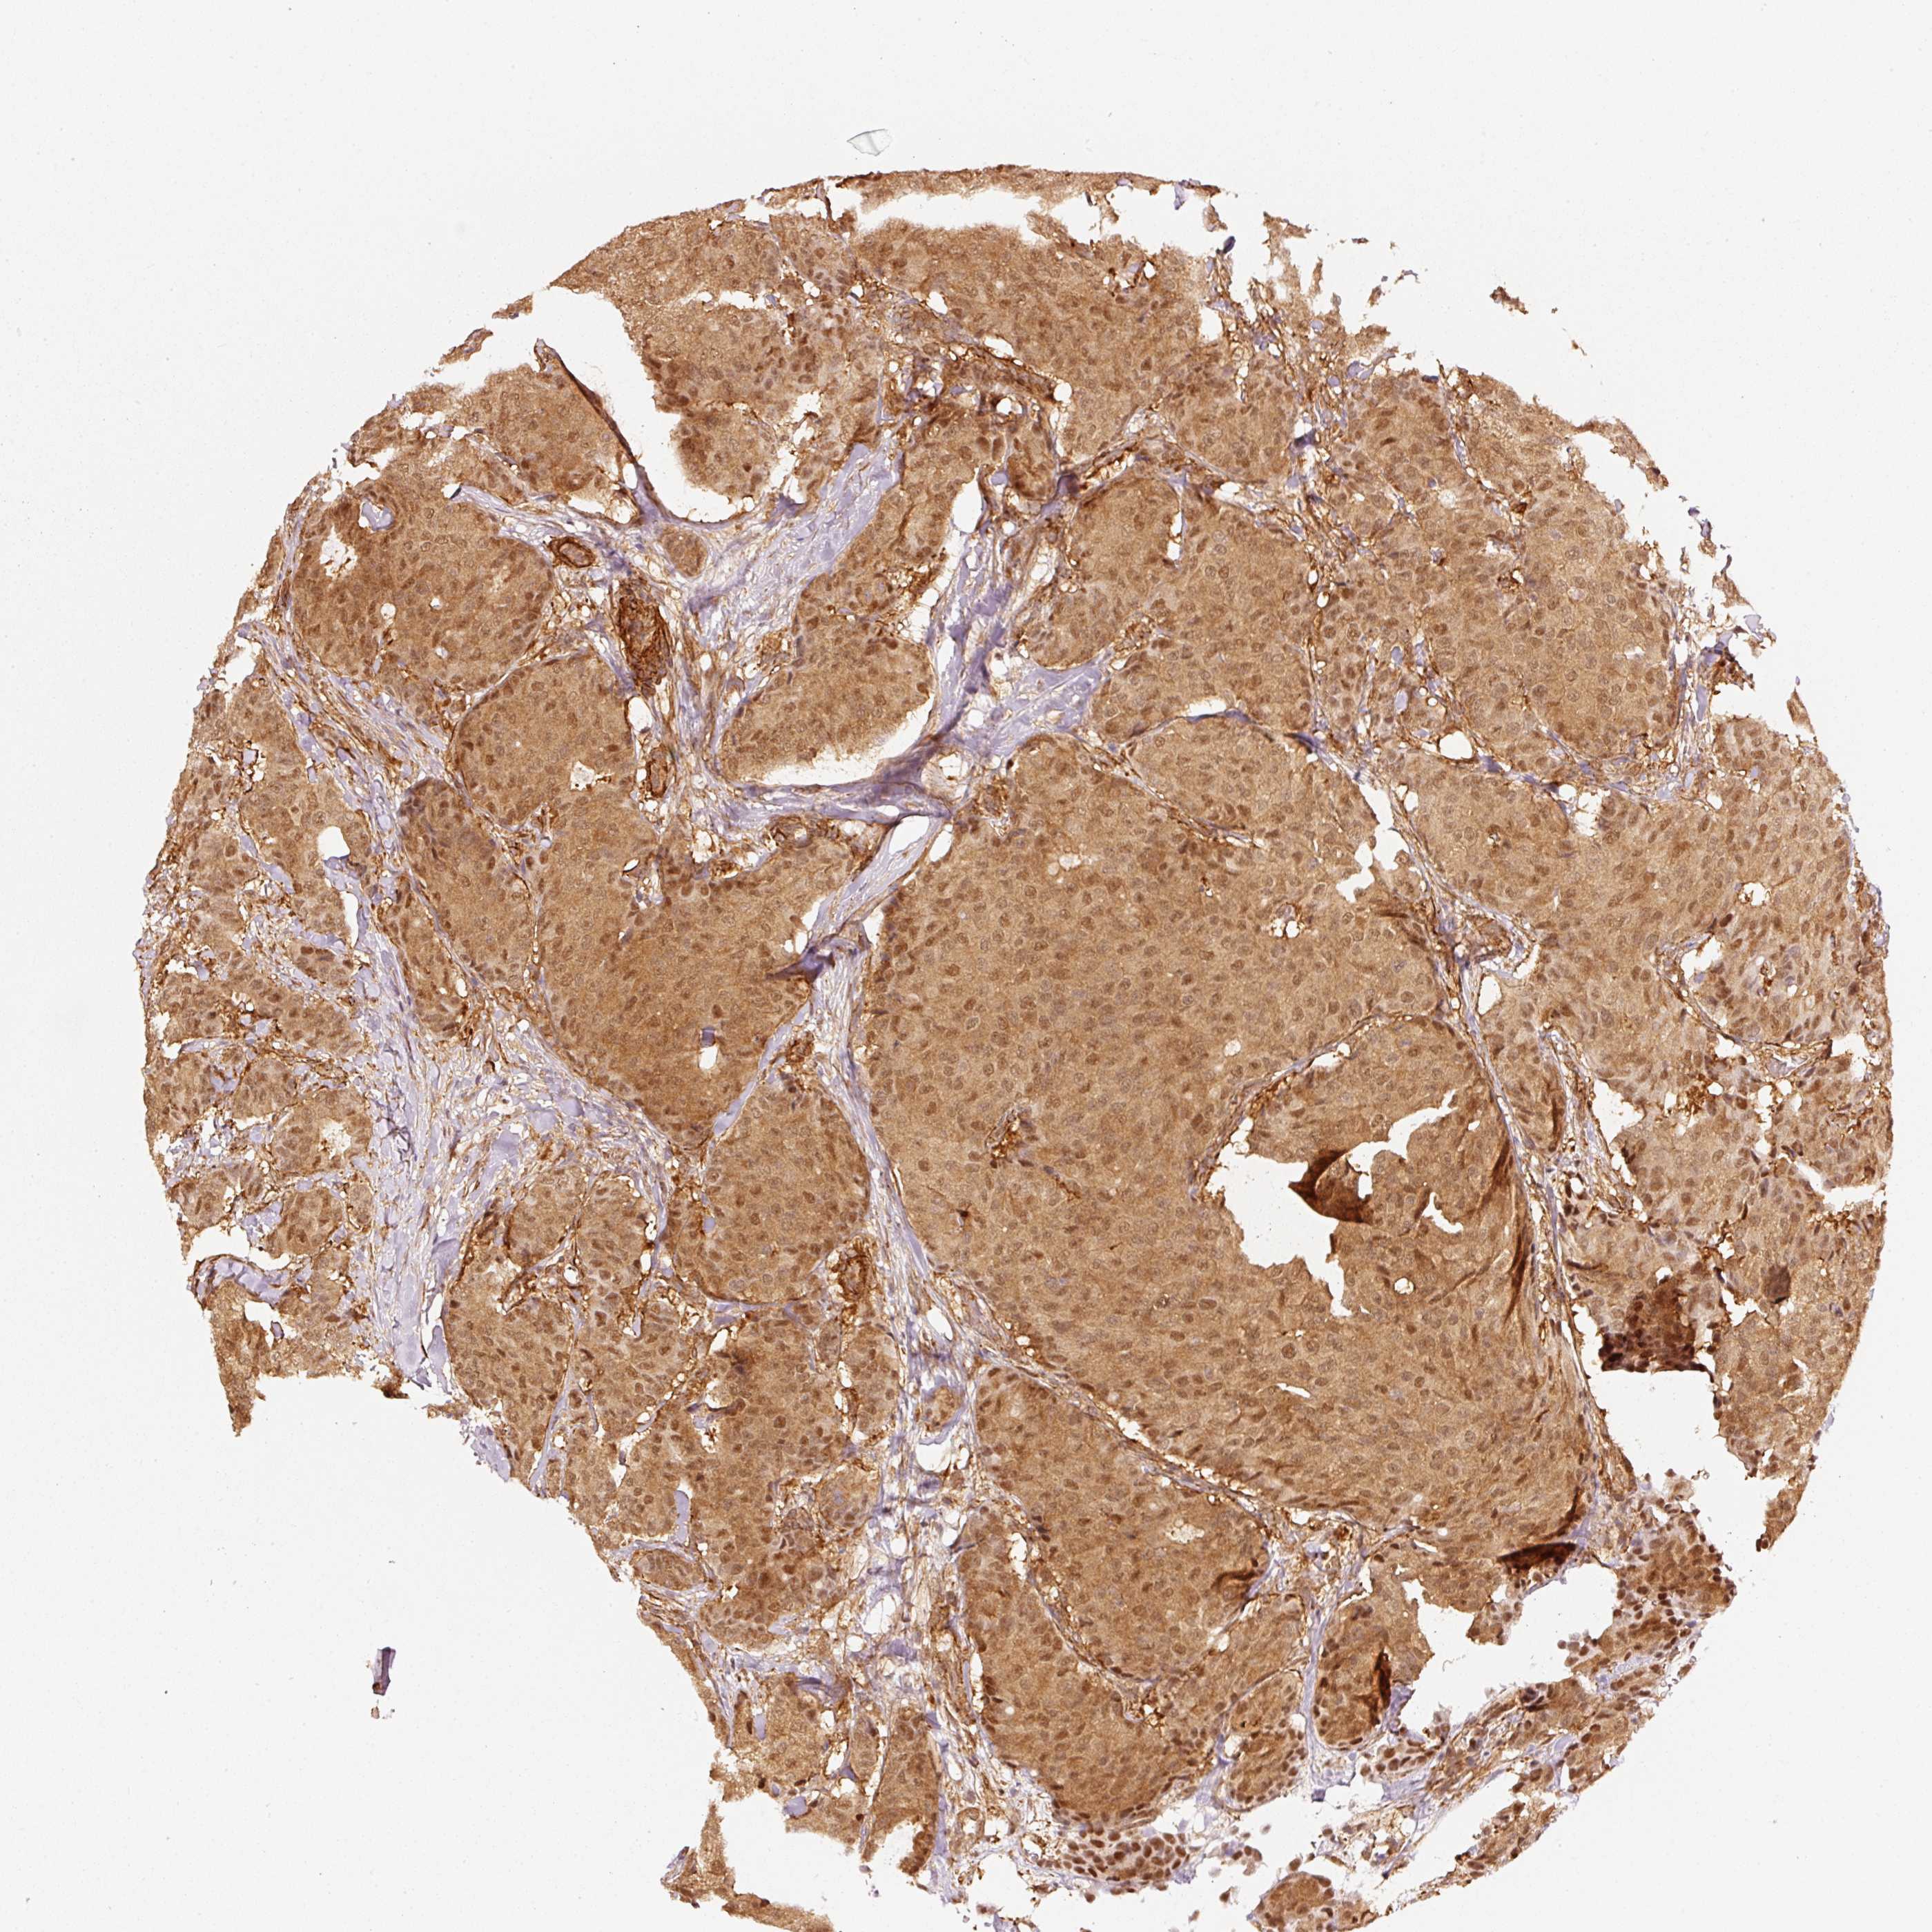

CANCER BREAST CANCER Show tissue menu

BRCA TCGA BRCA VALIDATION PROTEIN EXPRESSION